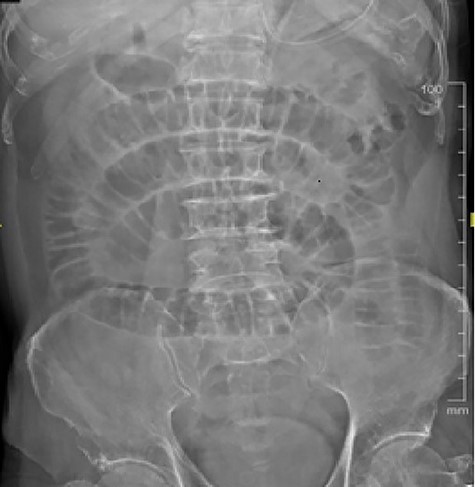

An 86-year-old Chinese gentleman presented with 1 day history of vomiting and colicky abdominal pain. He had underlying hypertension and cerebrovascular accident >10 years ago. On examination, his abdomen was distended but soft. There was mild tenderness at paraumbilical region. However, there was no guarding or rebound tenderness. Nasogastric tube was inserted and 400 cc of feculent material drained. His blood investigations revealed total white blood count of 14.3 × 109/l, lactate 5, urea 10.6 mmol/l and creatinine 119 μmol/l. Arterial blood gas showed a compensated metabolic acidosis with pH 7.36, bicarbonate 20.4 mmol/l and base excess −4.4. Abdominal X-ray showed dilated small bowel (Fig. 1), and contrast-enhanced computed tomography (CT) of the abdomen showed dilated small bowel with transition point at distal ileum. There was circumferential wall thickening at left iliac fossa. After 1 l of fluid resuscitation, repeated lactate remained raised at 5.5, which raised the concern of bowel ischaemia. Thus, emergency exploratory laparotomy was performed. Intraoperatively, an intraluminal mass was noted 7 cm proximal from the terminal ileum (Fig. 2). An enterotomy was done and revealed a piece of mushroom (Fig. 3). Retrospectively, upon further questioning, patient had poor dentition and had swallowed a mushroom 6 days ago on Chinese New Year Eve when family members from near and far gather for a reunion dinner.